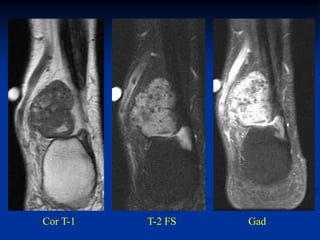

Case #1188

72 year female with

intramuscular lipoma

mid arm

Axial T-1 MRI

Case #1188 72 yearfemale with intramuscular lipoma mid arm